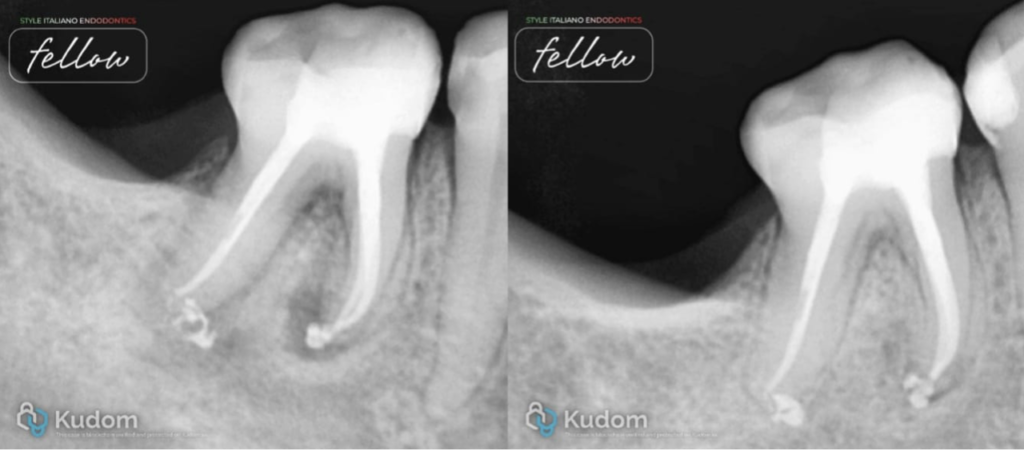

The patient reported to our office with a complaint of food lodgement in the lower right back teeth region. During oral examination, proximal caries was found in the lower first molar. There was no pain in the molar tooth. In a radiographic examination there were periapical lesions in both roots. The tooth did not respond to the cold test. A necrotic tooth with a periapical lesion and no pain as symptoms suggest asymptomatic apical periodontitis.

Fig. 1

A preoperative x-ray shows proximal caries extended into the pulp and causing periapical lesion in the mesial and distal roots of the lower first molar. Non-surgical endodontic treatment was planned.